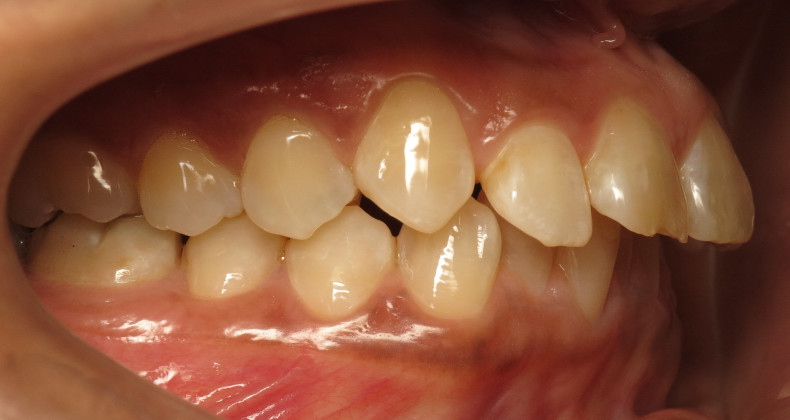

Der intraorale Befund (Abb. 2a–e) sowie die Modellanalyse (Abb. 3a–e) zeigten neben dem Diastema mediale im Oberkiefer vor allen Dingen eine Anteinklination und Supraokklusion beider Fronten. Besonders anterior wiesen beide Zahnbögen eine transversale Enge auf. Dies zeigte sich in einem deutlichen Unterkieferfrontengstand mit Labialkippung des Zahnes 41. Neben Abrasionen und Schlifffacetten, vor allem in der Front, waren auch vereinzelt Gingivarezessionen erkennbar. An Zahn 11 lag eine Schmelzfraktur der Inzisalkante vor. Durch die zwangsgeführte Laterognathie ergab sich eine Mittellinienverschiebung nach rechts von 3 mm. Eine beidseitige Distalokklusion bei vergrößerter sagittaler (6 mm) und vertikaler (5 mm) Stufe war erkennbar. Aufgrund der deutlichen transversalen Zahnbogenenge im Unterkiefer ergab sich links eine Tendenz zum Scherenbiss.